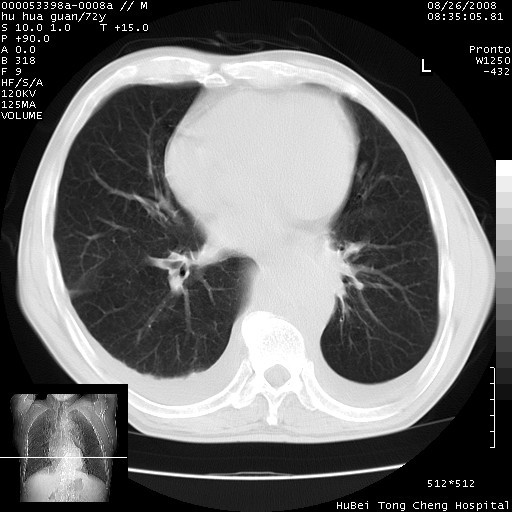

标题: CT15582:M,72Y。请老师帮分析胸部病变。

可以明确的说。肯定不是主动脉夹层破裂出血!考虑为淋巴瘤或间叶组织来源的恶性肿瘤可能性大。右肺小结节建议薄层观察,如能发现恶性征象,那椎前改变就考虑为转移所致。至于双侧少量胸水乃静脉血回流受阻所致。

1、右上肺结节病变,肺泡癌不除外,请随诊;左下肺近后纵隔病变,考虑纵隔型肺癌侵犯大血管可能;

2、右下肺背段少许炎症,双侧胸腔积液,右下肺纤维索条。

降主动脉前移位,后纵隔占位

后纵隔占位,降主动脉前移位;双侧胸腔积液;应排外食管病变侵犯血管可能;